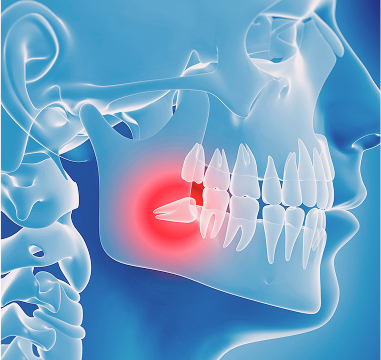

사랑니발치,

잇몸 속에 묻히거나 비뚤게 난 사랑니를 안전하게 제거하는 시술입니다.

CT로 신경 위치를 확인해 통증과 부작용을 최소화합니다.

사랑니가 잇몸 속에 일부만 나와 음식물이 자주 끼는 경우

잇몸 주변에 염증이 생기거나 통증이 반복되는 경우

옆 치아를 밀어 충치나 치아 이동이 생길 수 있는 경우

치아 배열이나 교합(물림)에 영향을 주는 경우

교정치료 전·후로 공간 확보가 필요한 경우